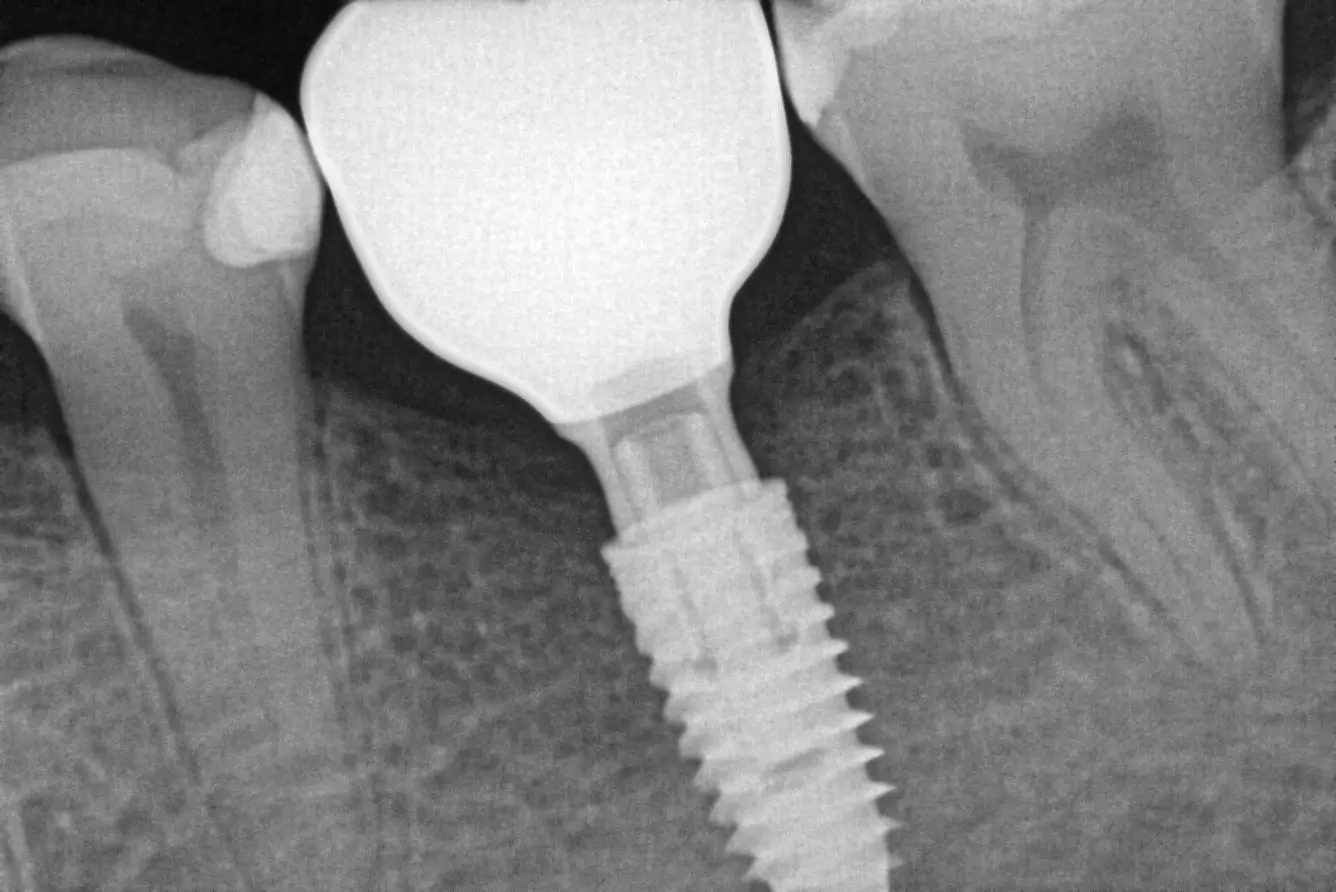

Імплантація з відновленням анатомії зуба

Для відновлення функції втраченого зуба проведено імплантацію з подальшим формуванням ясен під майбутню коронку.

Завдяки цифровому оптичному відбитку виготовлено коронку, що точно відтворює анатомію природного зуба.

Фінальний етап — фіксація та делікатна корекція прикусу.

Результат: стабільність, естетика та повноцінна функція жування.